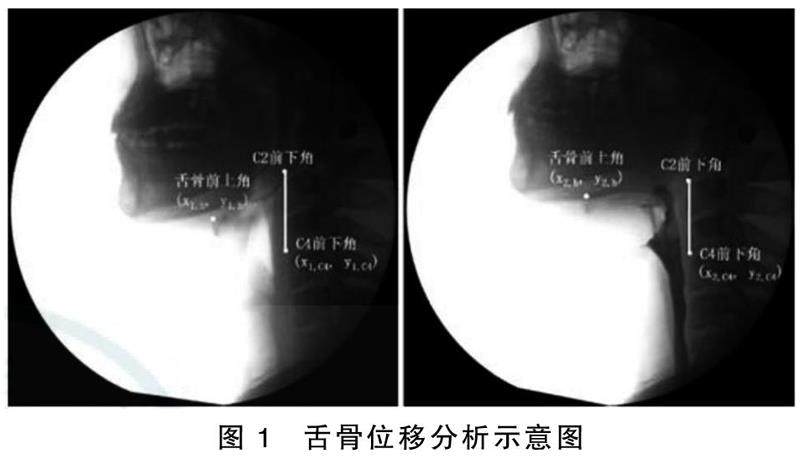

摘要目的:分析脑卒中吞咽困难病人吞咽造影特点并探讨其对误吸的预防作用。方法:选取2019年1月—2022年2月于我院进行住院治疗的235例脑卒中病人作为研究对象,按照是否发生吞咽困难分为吞咽困难组(112例)和吞咽正常组(123例)。通过吞咽造影定性观察两组病人拒绝进食、张口困难、口腔闭合不全、口腔残留、咽腔残留、渗漏、误吸等情况的发生率,并采用吞咽造影数字化采集分析系统对两组病人的时间学、运动学参数进行分析。(剩余9159字)